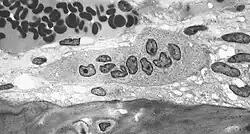

Transmissionselektronenmikroskopische Aufnahme (TEM) eines Osteoklasten in der Bildmitte. Die Mehrkernigkeit dieses knochenabbauenden Zelltyps ist gut sichtbar. -